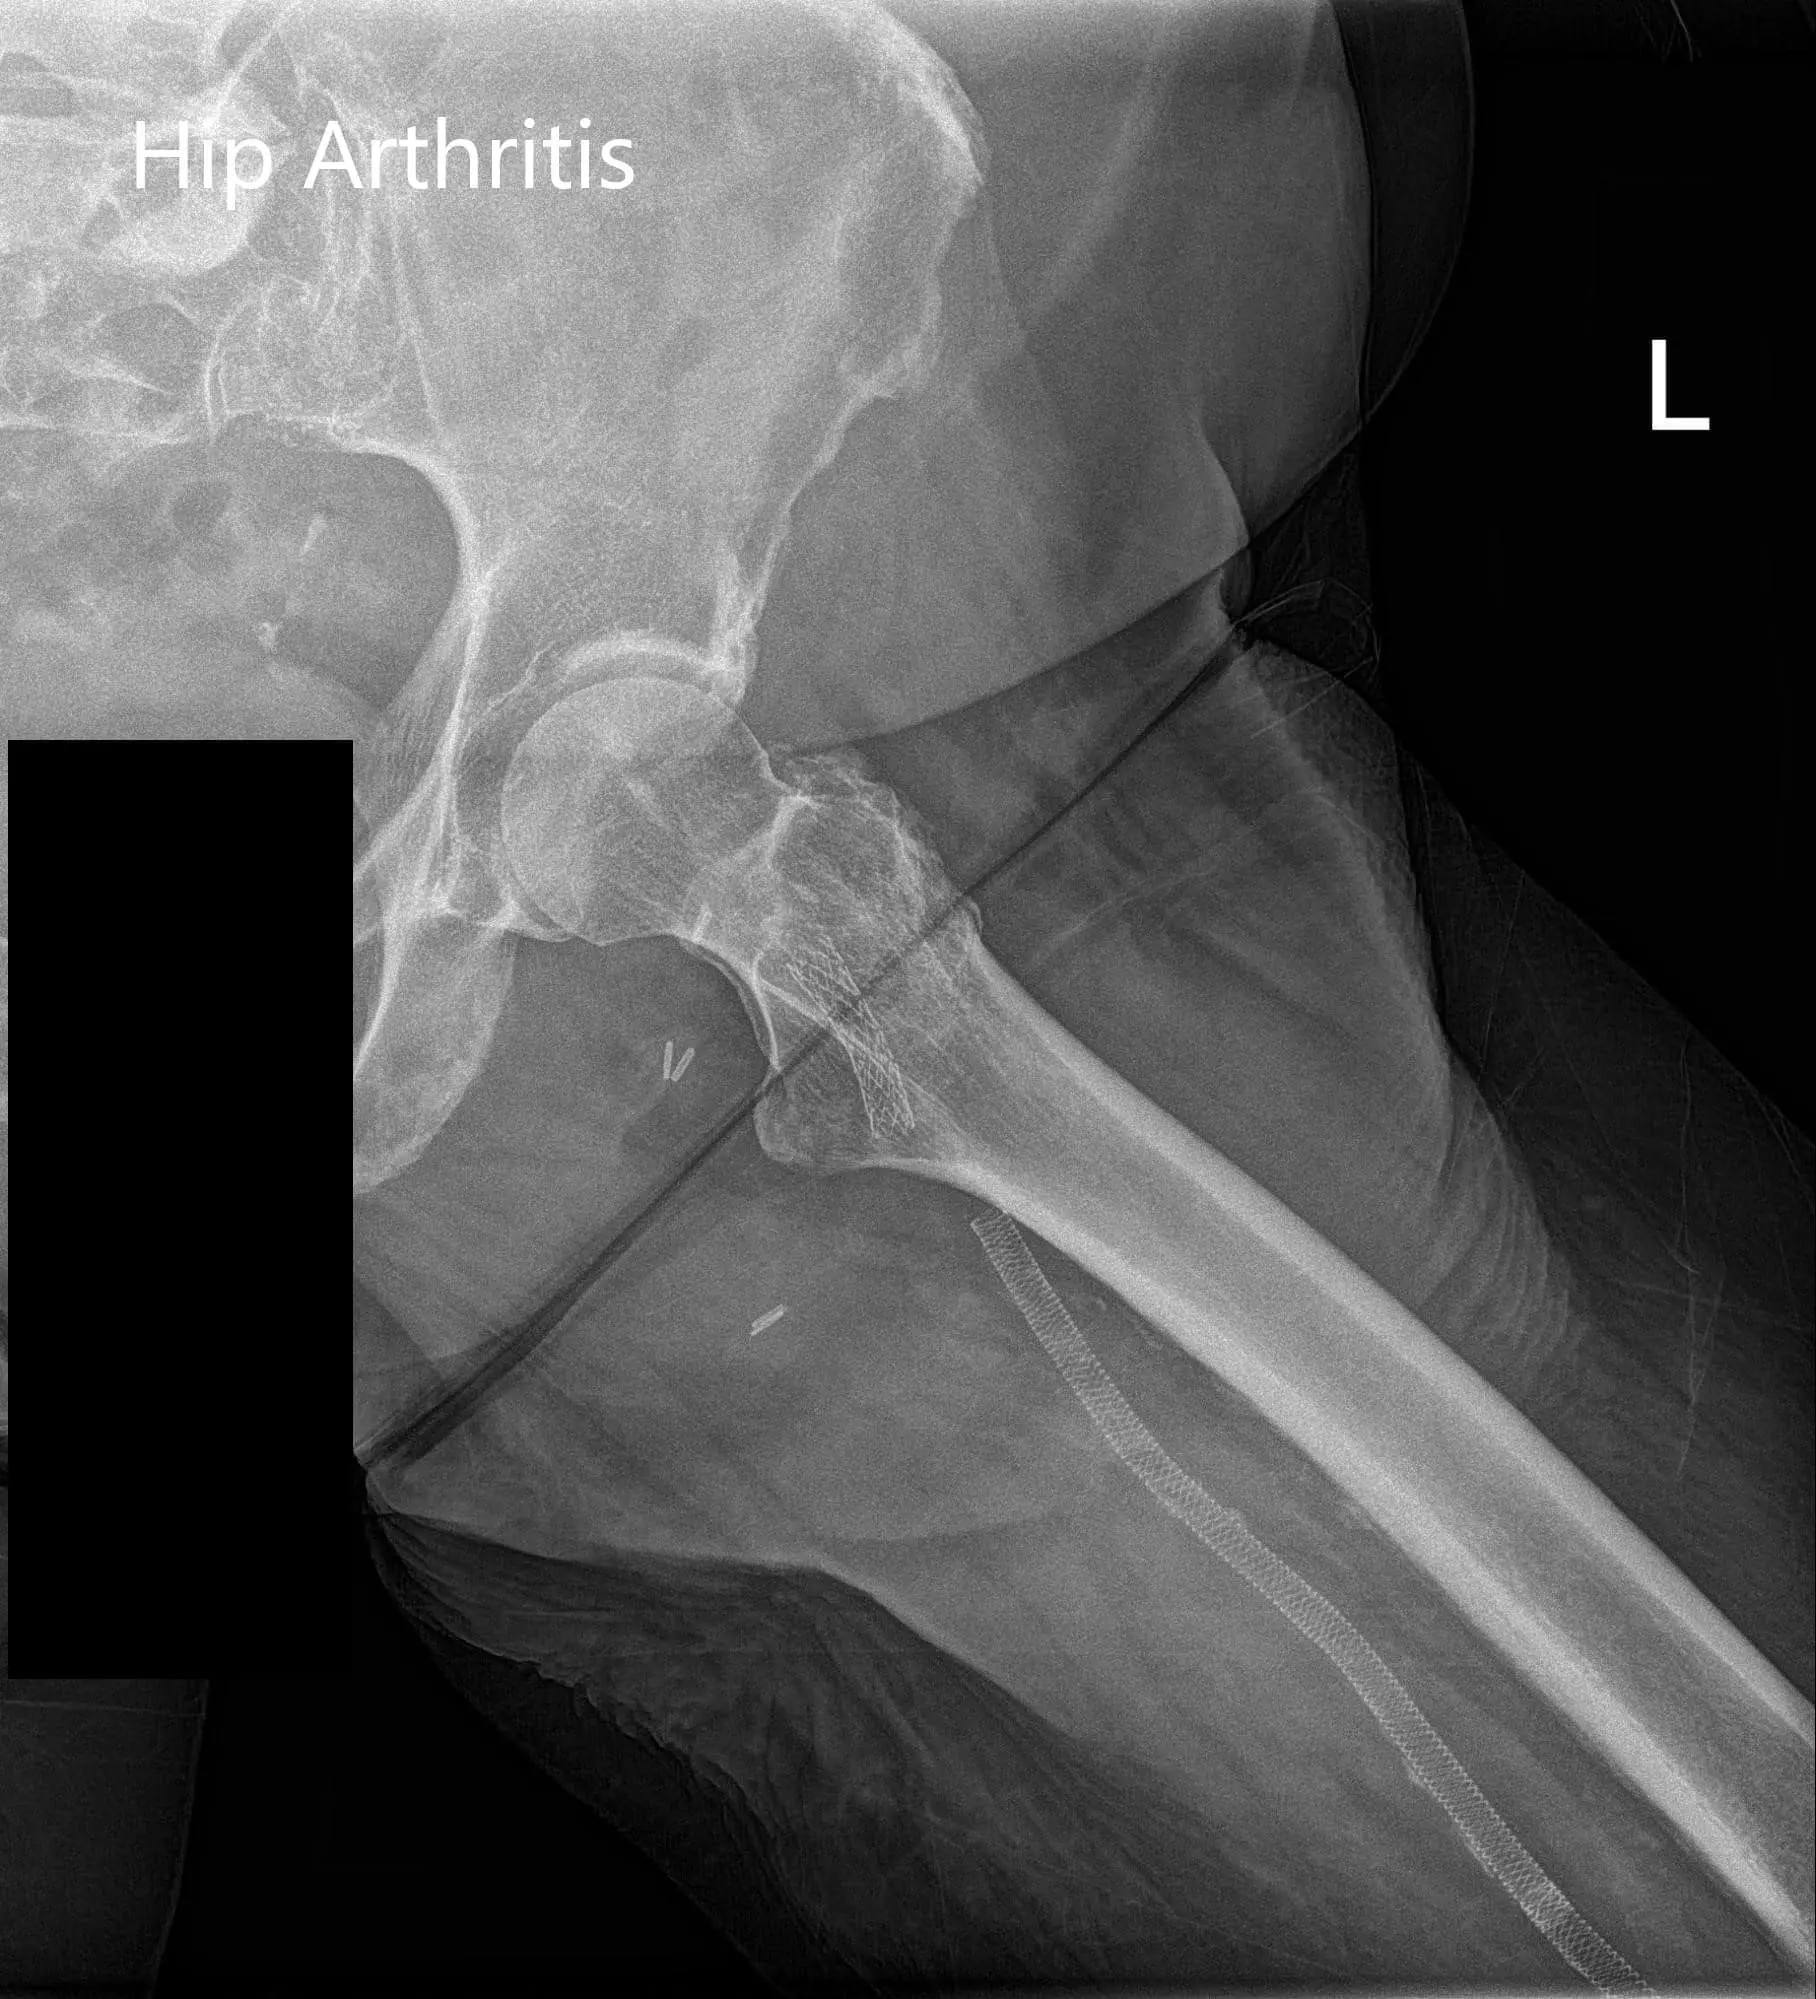

Imaging study revealed bilateral arthritis of the hip joint. There were severe degenerative changes on the left hip. After careful consideration of his cardiac risk factors, he was advised left total hip arthroplasty. Risks, benefits, and alternatives were discussed with him at length. He agreed to undergo left hip replacement.

Preoperative X-ray of the left hip showing AP and frog-leg lateral views